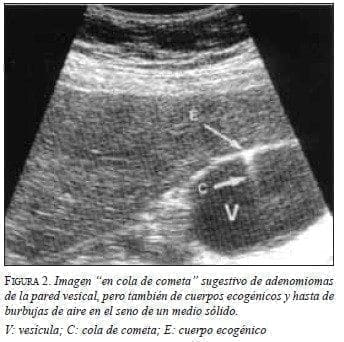

El diagnóstico preoperatorio es difícil y generalmente ambiguo, puesto que en los casos con importante sintomatología siempre se sospechará una lesión maligna que puede someterse a una resección quirúrgica amplia. En la afectación difusa de la vesícula biliar, la ecografía puede revelar engrosamiento de la pared con pequeñas zonas quísticas anecoicas que representan los senos de Rokitansky-Aschoff 17, los cuales pueden contener pequeños cálculos. Un ecografista experimentado podría obtener un alto índice de sospecha de adenomioma, pues este produce un signo radiológico muy sugestivo, denominado “cola de cometa” (figura 2) 8. La forma seg-mentaria puede confundirse con colecistitis o carcinoma, aunque también es posible la coexistencia de ambas.